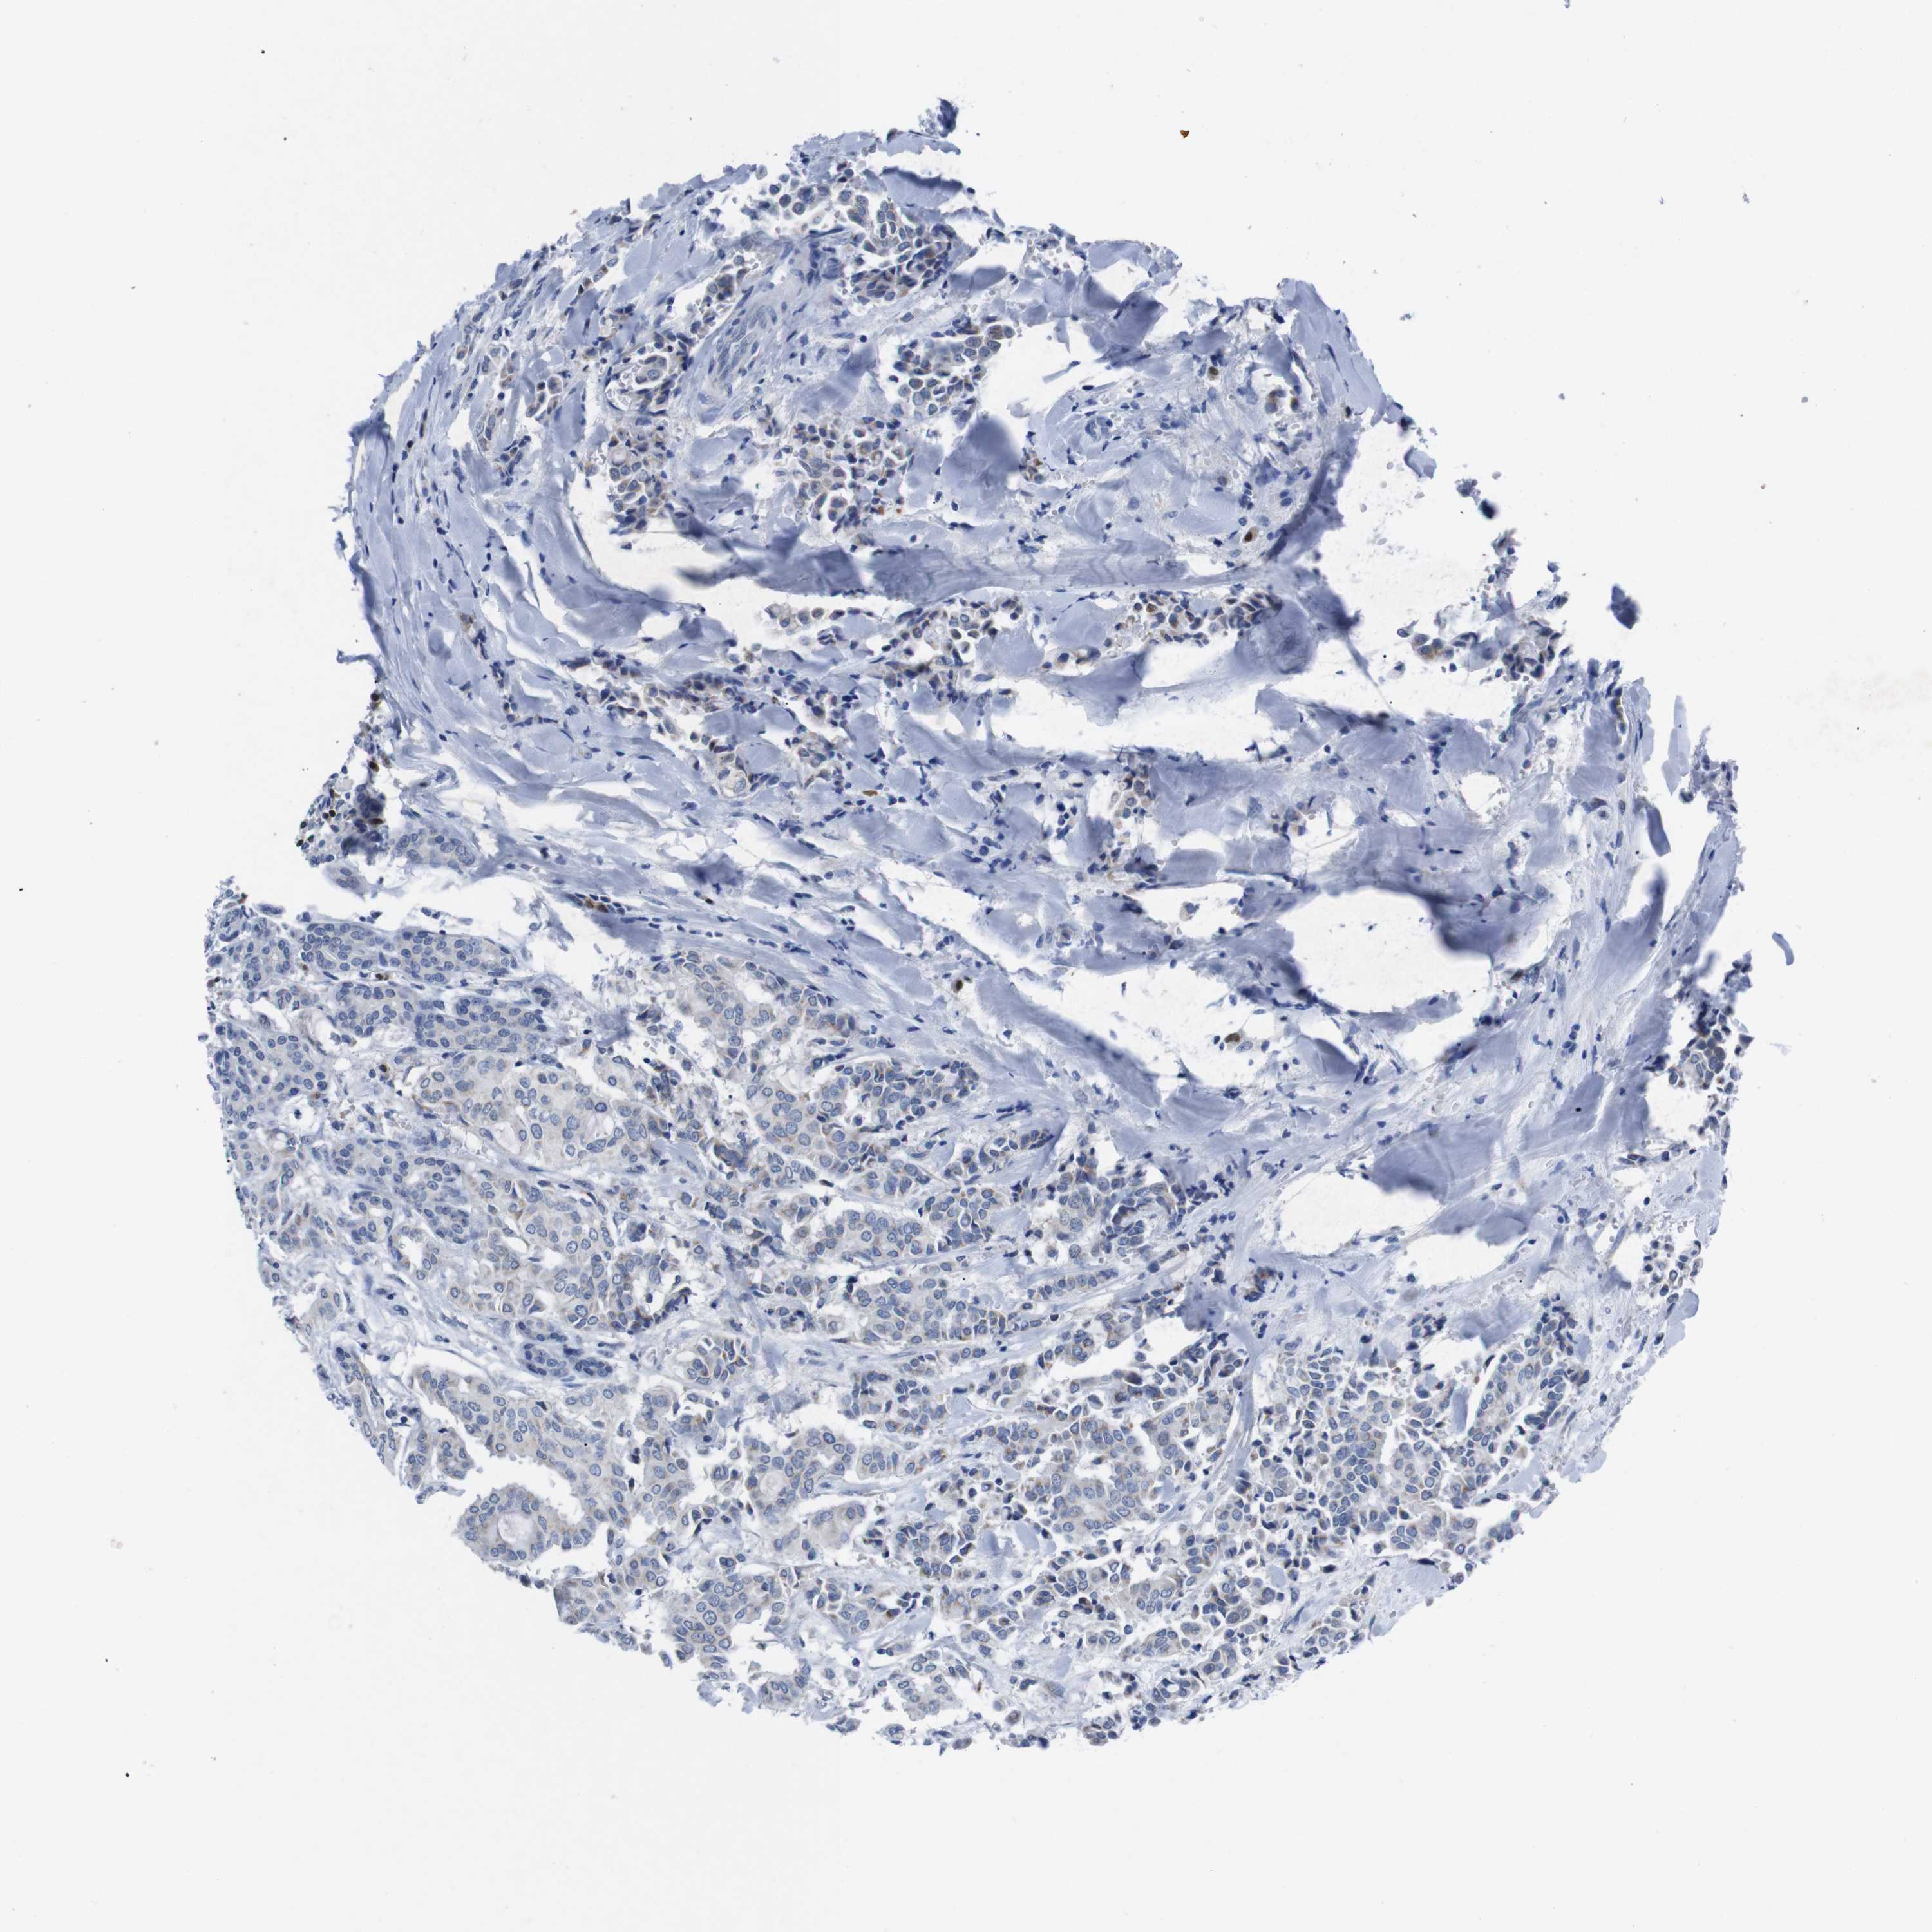

HEAD AND NECK CANCER - Protein expressioni

A mouse-over function shows sample information and annotation data. Click on an image to view it in a full screen mode. Samples can be filtered based on level of antibody staining by selecting one or several of the following categories: high, medium, low and not detected. The assay and annotation is described here.

Note that samples used for immunohistochemistry by the Human Protein Atlas do not correspond to samples in the TCGA dataset.

Antibody stainingi

Antibody staining in the annotated cell types in the current human tissue is reported as not detected, low, medium, or high, based on conventional immunohistochemistry profiling in selected tissues. This score is based on the combination of the staining intensity and fraction of stained cells.

Each image is clickable and will lead to virtual microscopy that enables deeper exploration of all samples and also displays staining intensity scores, fraction scores and subcellular localization as well as patient and tissue information for each sample.

Antibody HPA002038

Antibody HPA002698

Antibody CAB013508

Staining

High

Medium

Low

Not detected

Intensity

Strong

Moderate

Weak

Negative

Quantity

>75%

75%-25%

<25%

None

Location

Nuclear

Cytoplasmic/membranous

Cytoplasmic/membranous,nuclear

Squamous cell carcinoma, NOS

Neoplasm, malignant, NOS

Adenocarcinoma, NOS

Squamous cell carcinoma, metastatic, NOS